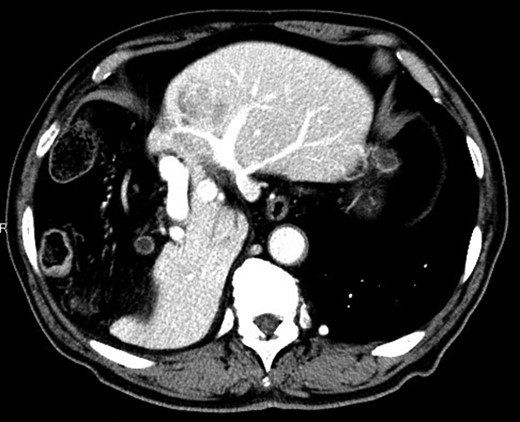

Considering the small remnant right lobe and abnormal ICG15, we planned to perform laparoscopic anatomical S3 segmentectomy. The procedures were performed using a pressure-controlled carbon dioxide pneumoperitoneum, which was maintained below 12 mmHg. Intraoperative findings showed hypoplasia of the right hepatic lobe and hypertrophy of the left hepatic lobe (Fig. 2). Intraoperative ultrasound (IOUS) was performed to confirm the location of the tumor and its relationship to the adjacent structures. The Glissonian pedicle to S3 was isolated with meticulous dissection and was then transected using the SigniaTM Stapling System and Endo GIATM Curved Tip Reload with Tri-StapleTM Technology 30 mm, Vascular Medium (Covidien, USA) (Fig. 3). The ischemic margin of S3 was marked using electrocautery (Fig. 4). Using the crush-clamp method with a harmonic scalpel (Ethicon, USA), the liver parenchyma was transected along the left hepatic vein (Fig. 5). Pringle’s maneuver was performed by clamping the hepatoduodenal ligament using the tourniquet method for 15 min with following a 5-min release period, and a total of fourteen temporary clamps were performed during parenchymal resection. The resected specimens were removed in a retrieval bag through an umbilical port site. The resected specimen showed a 41-mm simple nodular type of HCC and a 5-mm tumor-free resection margin (Fig. 6). Each port was placed as shown in Fig. 7.

The liver parenchyma was transected along the left hepatic vein.